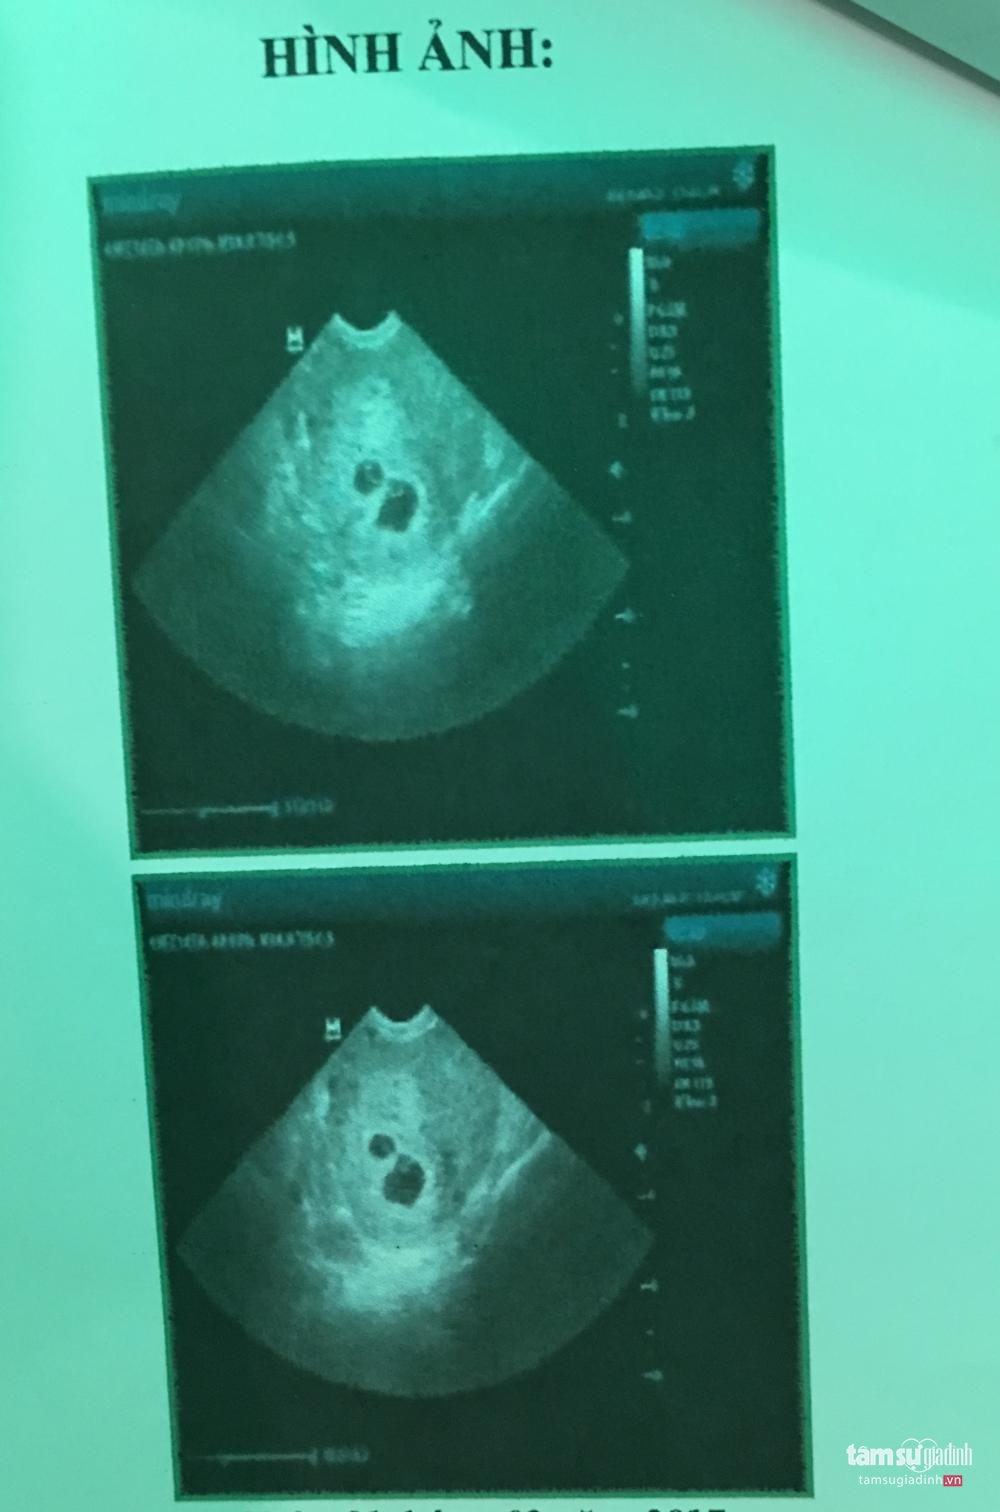

Sau đó, chị được đưa đến một căn phòng ở tầng 4. Một nữ bác sĩ người Trung Quốc bước vào và yêu cầu chị cởi quần ra để kiểm tra. “Qua một hồi xăm soi và hỏi qua loa vài câu, bác sĩ kết luận tôi bị hai phôi thai, vùng chậu ứ dịch. Sau đó bác sĩ nói phải tiến hành can thiệp loại bỏ bào thai, nếu không khi sinh ra đứa trẻ sẽ mang nhiều bệnh tật, hình hài xấu xí”, chị Tr. nhớ lại.

Kết quả siêu âm được cho là có hai bào thai dị tật cần phải được hút bỏ